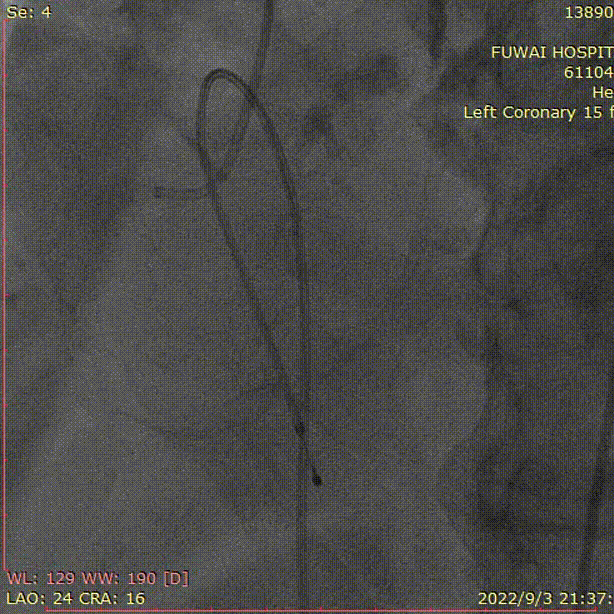

1、冠脉造影和抉择急诊PCI和急诊TAVR

左冠造影